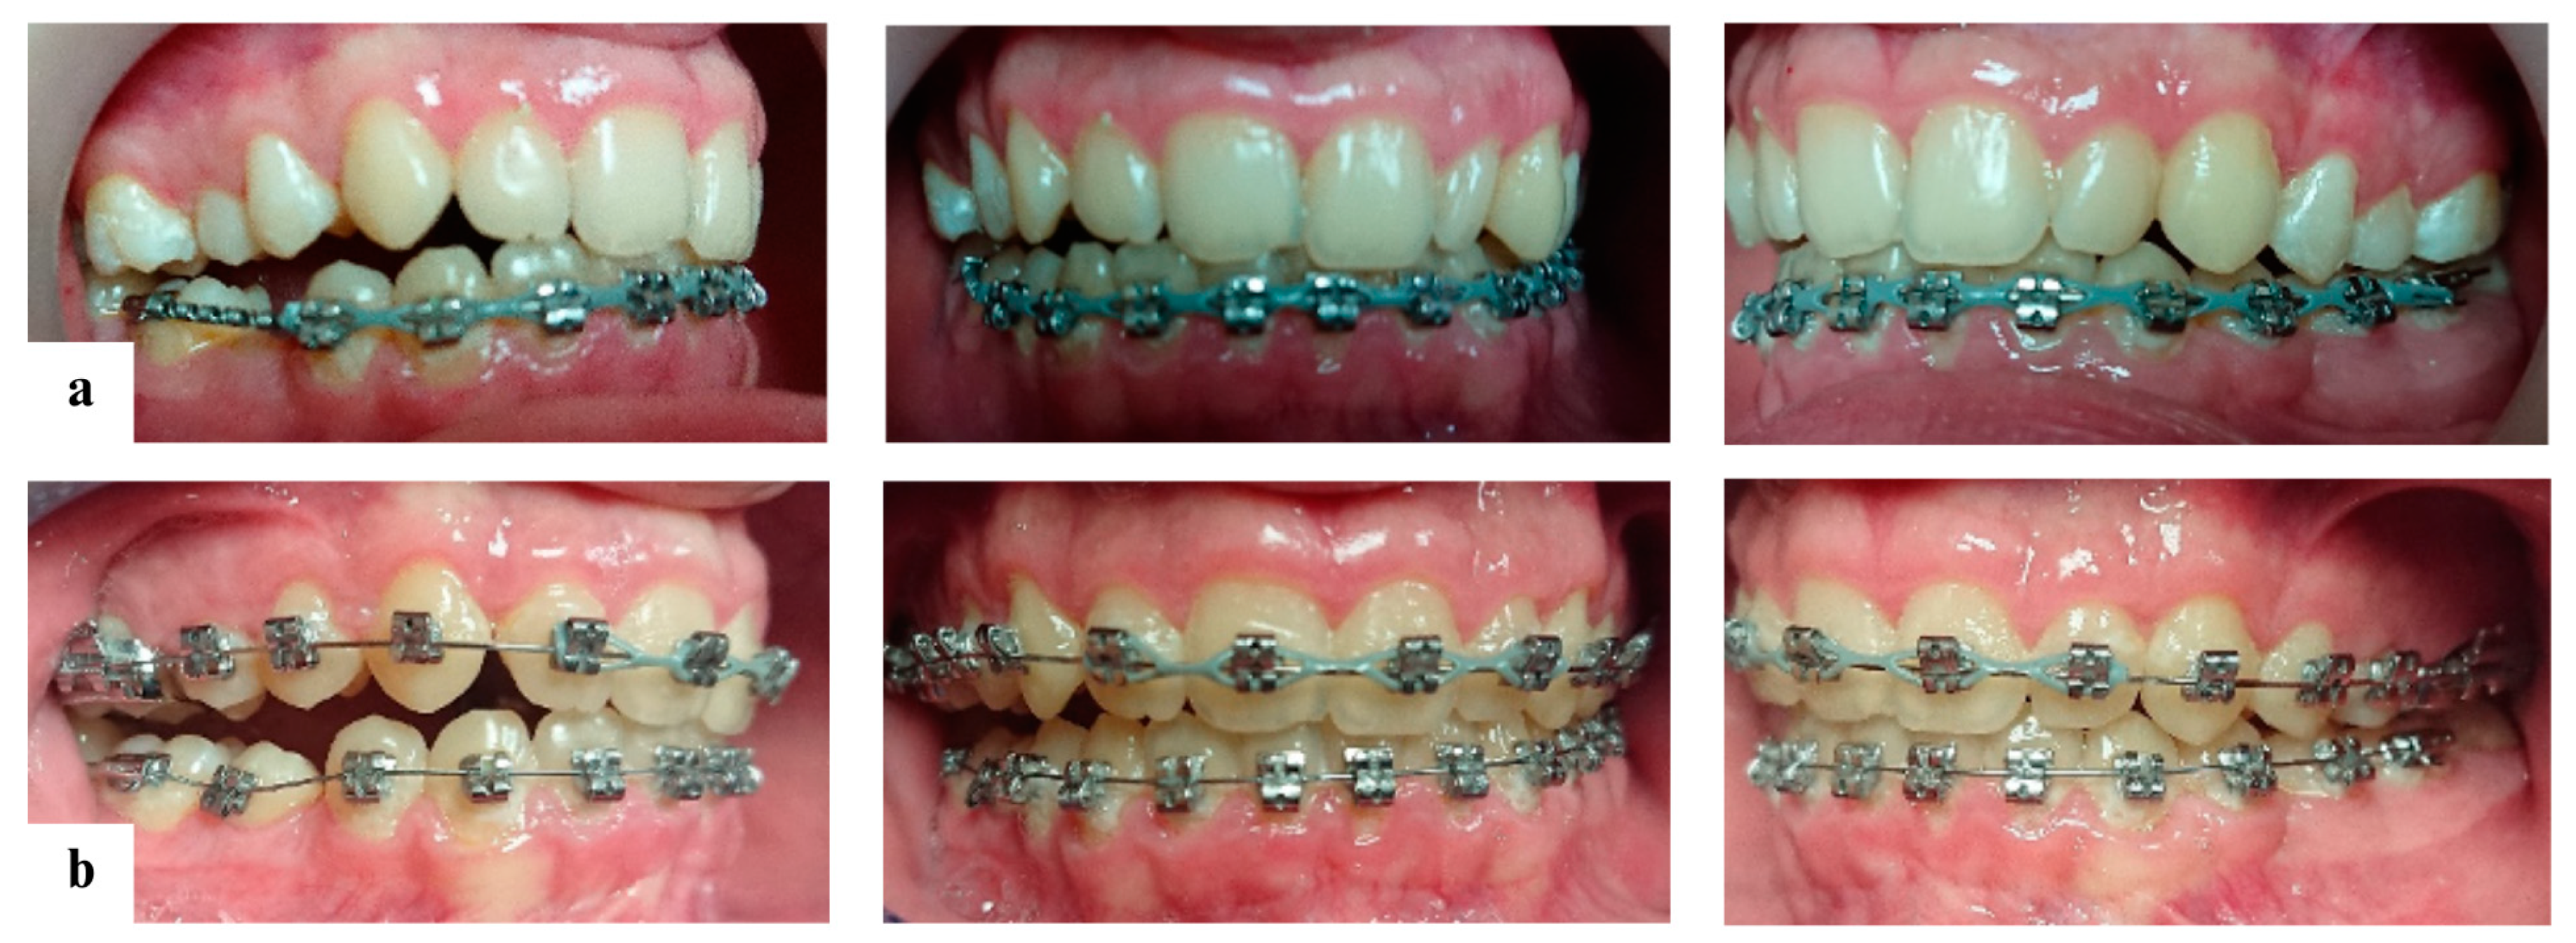

2.3. Treatment Progress